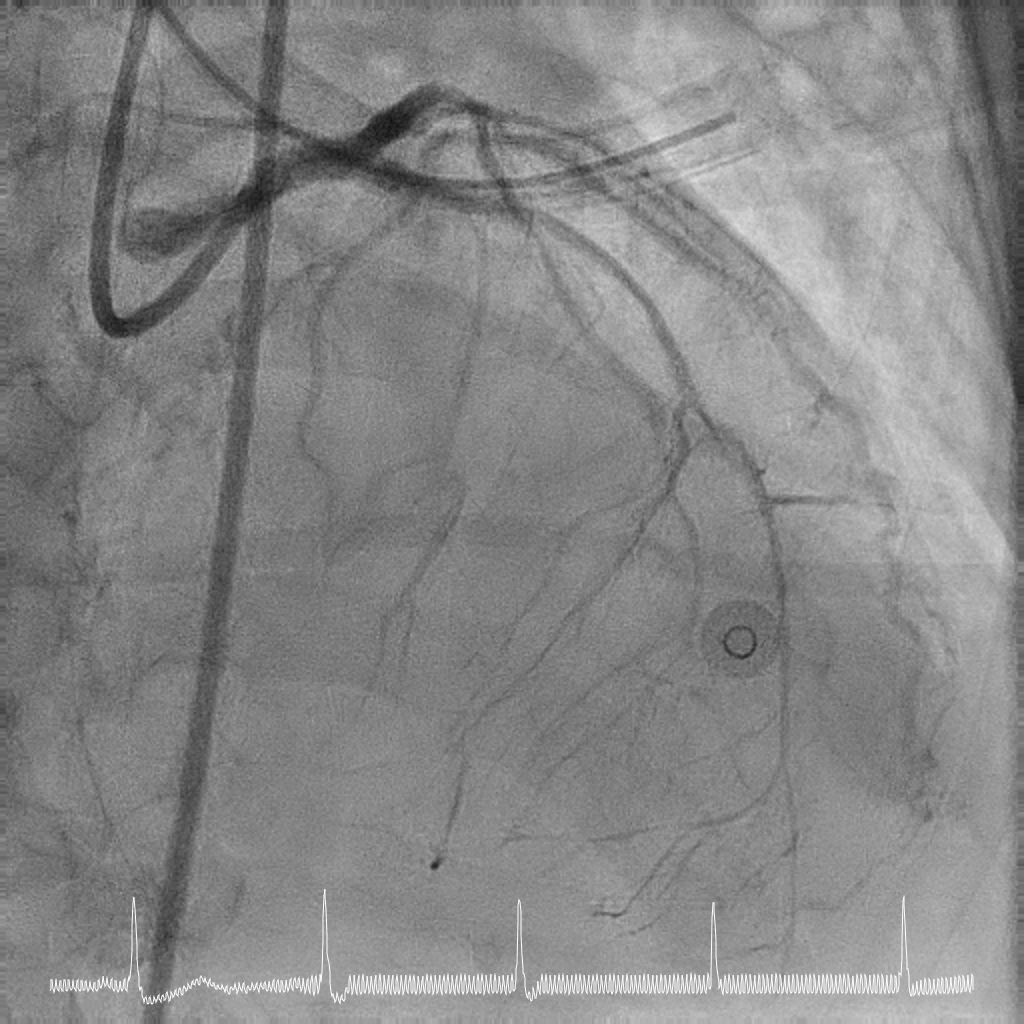

Rotational atherectomy with 1.5mm and then 2mm was performedfrom ostial LM to proximal LCx. Wiring of the LAD was only successful till midLAD with a separate distal LAD occlusion. LAD lesion was balloon uncrossableand half-way rotational atherectomy with 1.5mm burr. The distal LAD CTO wasthen crossed and balloon angioplasty undertaken. There was diffuse LAD disease, and the plan was then for ahybrid strategy. PCI to LM bifurcation was secured using the DK crushtechnique. 3.5x23mm Xience Sierra was placed in the LCx, 3.5x16mm Megatron inLM to proximal LAD followed by drug coated balloon angioplasty for the rest ofthe LAD with 2x40mm, 2.5x40mm, and 3x25mm balloon. She recovered well after her intervention and is infunctional New York Heart Association Class I, Canadian Cardiovascular Society Angina Grade 0. An elective angiogram was performed 6 months after indexprocedure to re-assess the results. This showed widely patient stents acrossthe LM-LAD-LCX, and excellent DCB results across the proximal to distal LAD andimprovement of her left ventricular ejection fraction.

This case illustrates the feasibility of a hybridrevascularisation strategy combining two-burr rotational atherectomy, left mainbifurcation stenting with DK crush, and downstream drug-coated balloonangioplasty in a patient with prohibitive surgical risk. Careful lesionpreparation and strategic device selection resulted in sustained long-termvessel patency and recovery of ventricular function in a patient with extreme-riskanatomy.